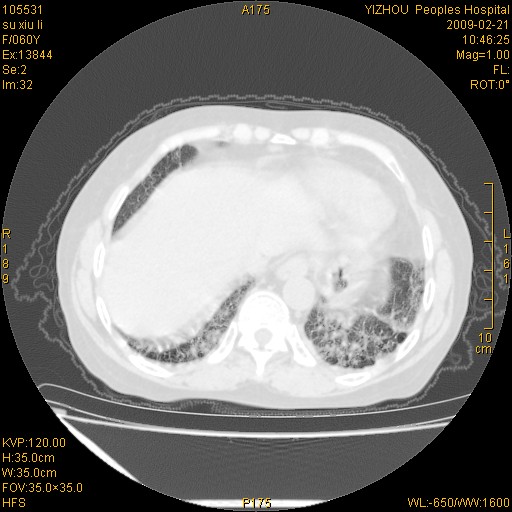

标题: CT18259:两肺间质纤维化? [打印本页]

标题: CT18259:两肺间质纤维化?

女,60岁,反复咳嗽1月。

两肺支扩,以肺为著合并双肺较广范纤维化病变。建议除外结核等病变。

间质性肺炎

符合间质感染,部分纤维化表现

特发性间质纤维化

特发性间质纤维化伴支扩!